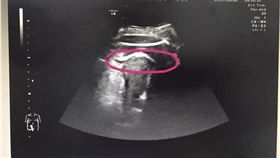

她懷孕八個月 遭腹中子踢破子宮…

肚子裡的胎兒踢破子宮,有可能嗎?中國大陸一名張姓產婦...